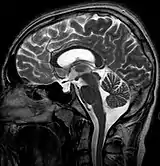

| MRI of Empty Sella | |